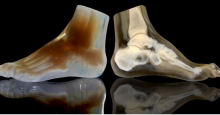

"The cosmetic and functional outcome of the surgery would have been significantly inferior without the use of the 3D technology."